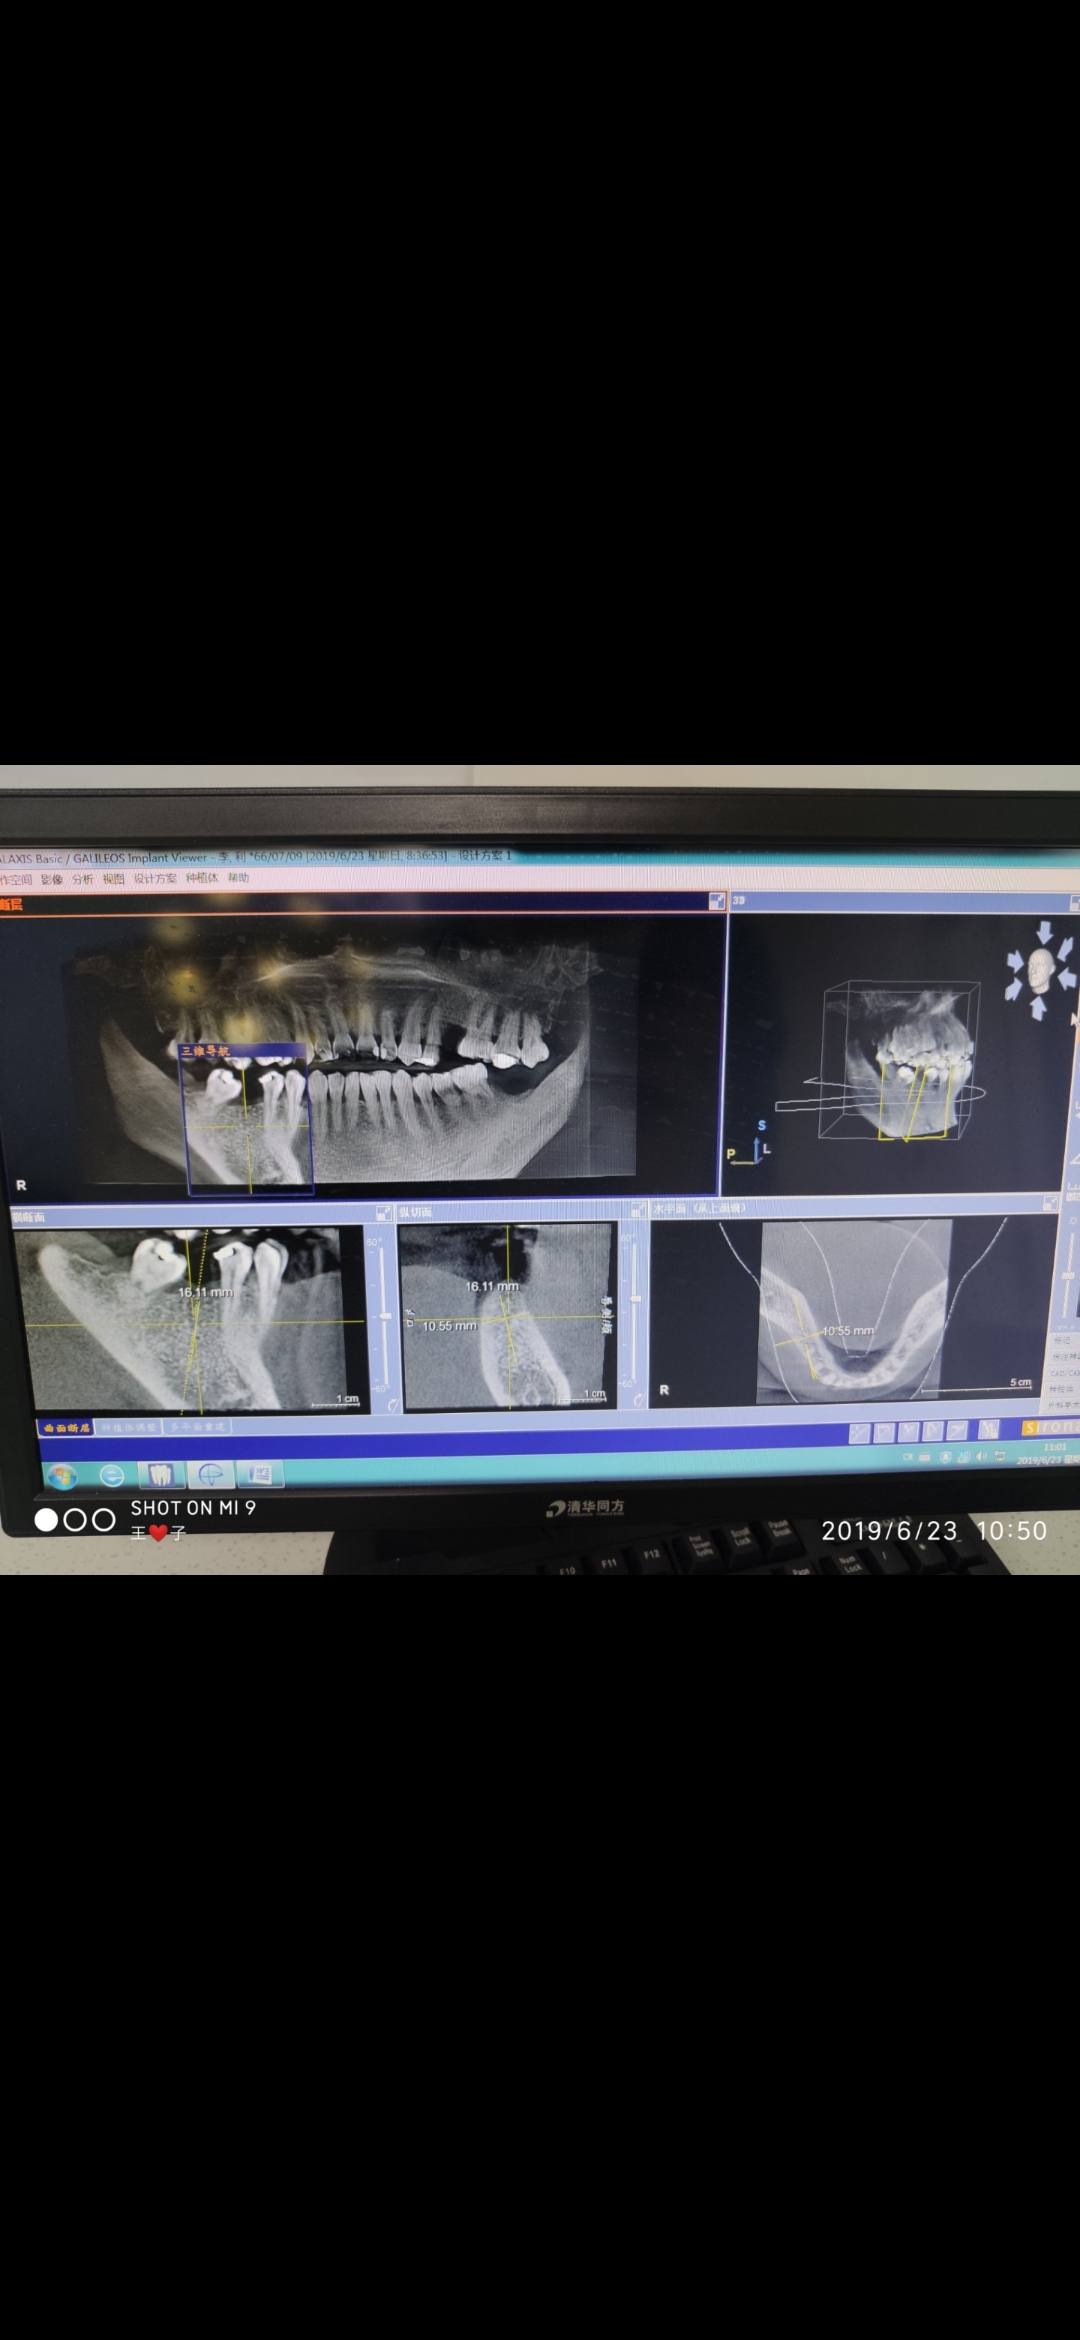

口腔ct可以从三维视角来查看口腔情况

口腔CT可重建口腔全景图像和各方位断层图像,图像清晰直观,用于种植牙术前测量、埋伏牙、肿瘤和口腔上颌窦瘘等多种疾病的诊断。